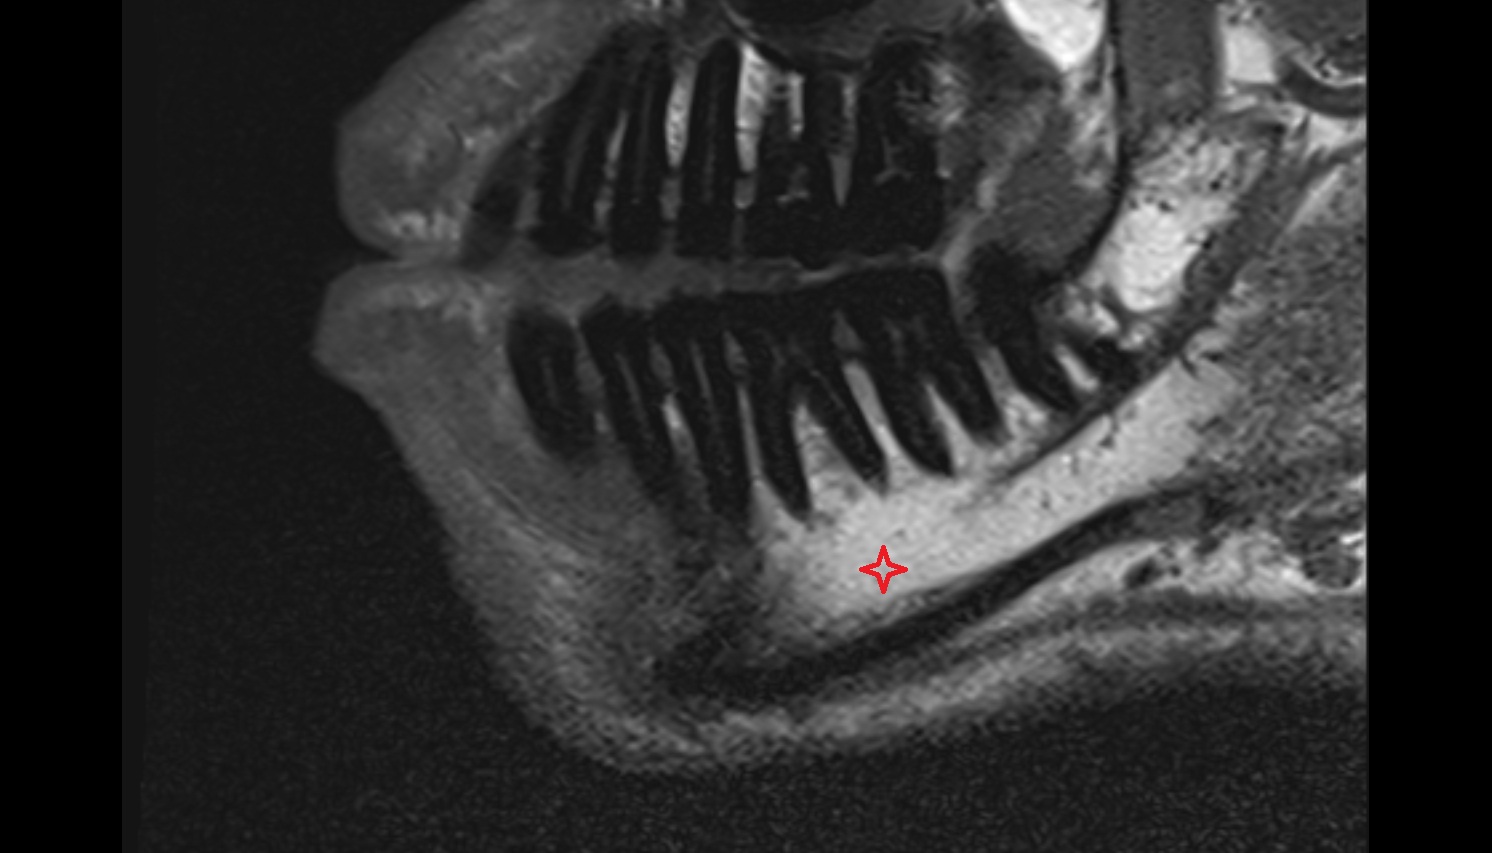

- Mandibular canal

- inferior alveolar artery

- Inferior alveolar nerve

- Mental nerve

- Body of mandible

- Inferior alveolar foramen (mandibular foramen)

- Mandibular foramen

- Root of lower molar tooth

- Lower molar apical foramen

- Mandibular nerve

- Dental branches of inferior alveolar artery, vein, & nerve